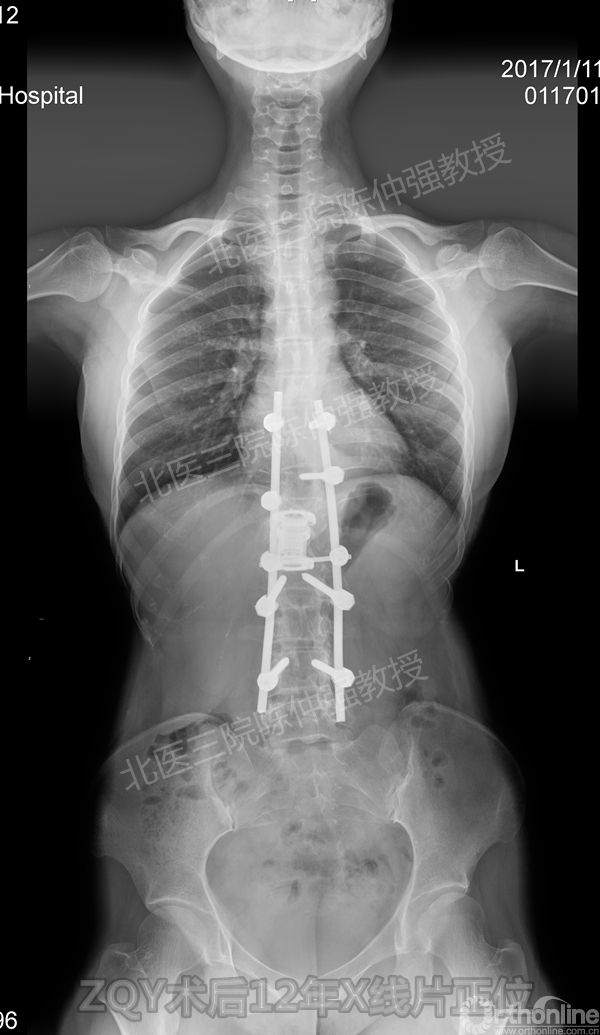

2005年,陈仲强教授在AOSpine年会上分享了一例胸腰椎陈旧结核性侧后凸畸形病例。资料如下:

患者女性17岁,胸腰椎陈旧结核性侧后凸畸形,局部呈“麻花状”扭转,无神经功能受损表现。2005年,陈仲强教授带领团队实施后路+侧前方联合入路脊柱节段切除、双轴旋转矫形术。术后患者外观显著改善,神经功能正常。术后随访证实患者截骨矫形节段骨性融合良好,矫形效果持续良好。